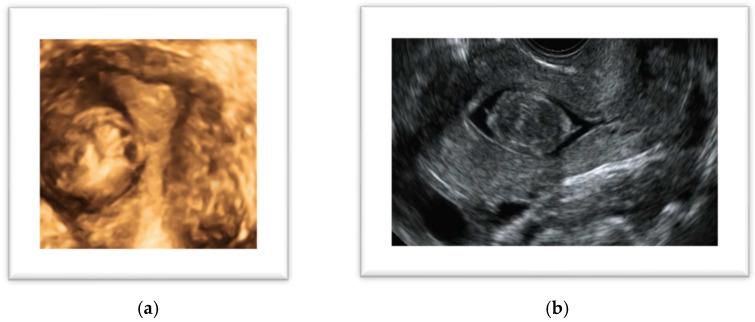

Uterine leiomyomas are the most common benign uterine tumors in women and are often asymptomatic, with clinical manifestation occurring in 20-25% of cases. The diagnostic pathway begins with clinical suspicion and includes an ultrasound examination, diagnostic hysteroscopy, and, when deemed necessary, magnetic resonance imaging. The decision-making process should consider the impairment of quality of life due to symptoms, reproductive desire, suspicion of malignancy, and, of course, the woman's preferences. Despite the absence of a definitive cure, the management of fibroid-related symptoms can benefit from various medical therapies, ranging from symptomatic treatments to the latest hormonal drugs aimed at reducing the clinical impact of fibroids on women's well-being. When medical therapy is not a definitive solution for a patient, it can be used as a bridge to prepare the patient for surgery. Surgical approaches continue to play a crucial role in the treatment of fibroids, as the gynecologist has the opportunity to choose from various surgical options and tailor the intervention to the patient's needs. This review aims to summarize the clinical pathway necessary for the diagnostic assessment of a patient with uterine fibromatosis, presenting all available treatment options to address the needs of different types of women.

子宫平滑肌瘤是女性最常见的良性子宫肿瘤,通常无症状,仅20% - 25%的病例会出现临床表现。诊断流程始于临床怀疑,包括超声检查、诊断性宫腔镜检查,必要时还包括磁共振成像。决策过程应考虑症状对生活质量的损害、生育意愿、恶性肿瘤怀疑,当然还有患者的偏好。尽管尚无根治方法,但子宫肌瘤相关症状的管理可受益于各种医学疗法,从对症治疗到旨在减轻肌瘤对女性健康临床影响的最新激素药物。当医学治疗对患者并非最终解决方案时,它可作为桥梁为手术做准备。手术方法在肌瘤治疗中仍起着关键作用,因为妇科医生有机会从各种手术选择中进行挑选,并根据患者需求调整干预措施。本综述旨在总结子宫纤维瘤病患者诊断评估所需的临床路径,呈现所有可用治疗方案以满足不同类型女性的需求。